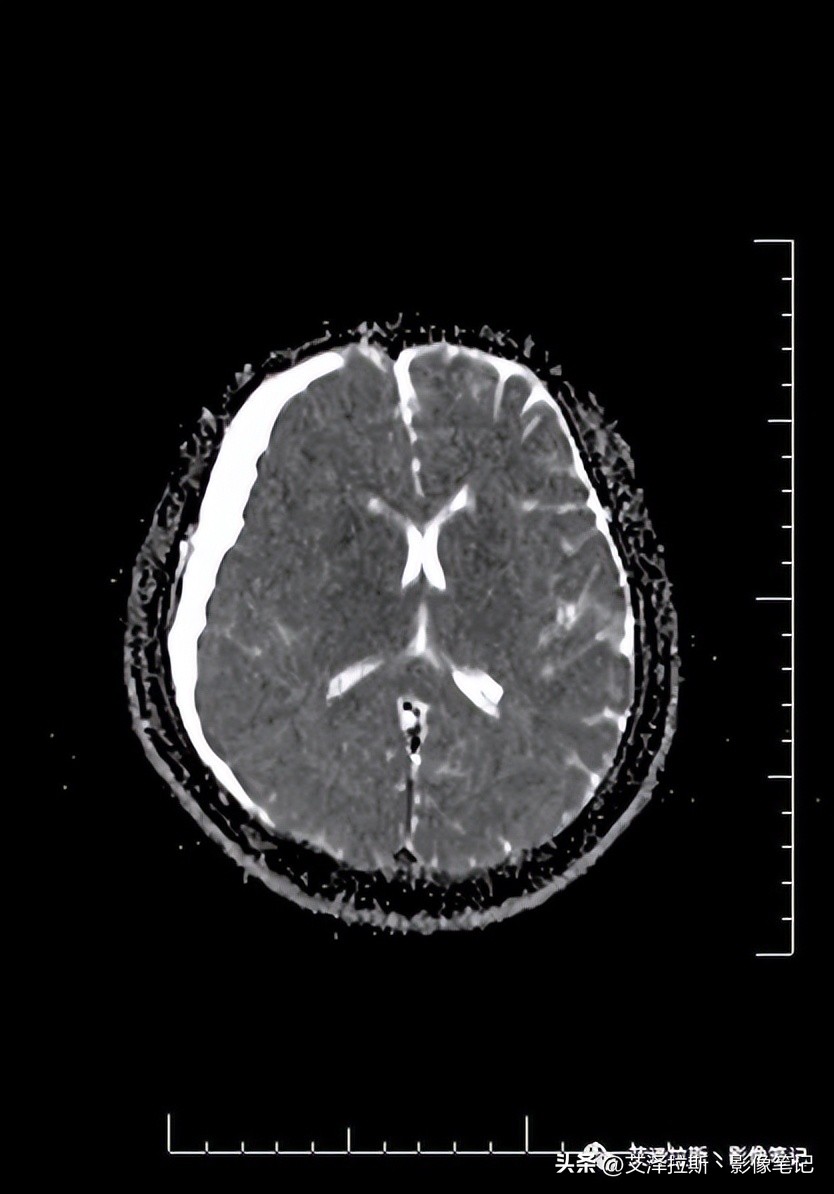

图7 T1+C TRA

图1-4显示右侧硬膜下血肿(亚急性-慢性期)、大脑镰硬膜下血肿(亚急性期),小脑幕硬膜下血肿(未提供图片);图7-9显示硬脑膜增厚,明显均一强化,未见结节状强化,柔脑膜未见强化。

低颅压综合征在影像上主要表现为四联征:

1.弥漫性硬脑膜增厚;

2.静脉窦扩张;

3.硬膜下积液/血肿

4.脑下垂,如小脑扁桃体疝等

在实际工作中,较少的病例具有典型的四联征,本例就未见脑下垂的影像表现(图6)。